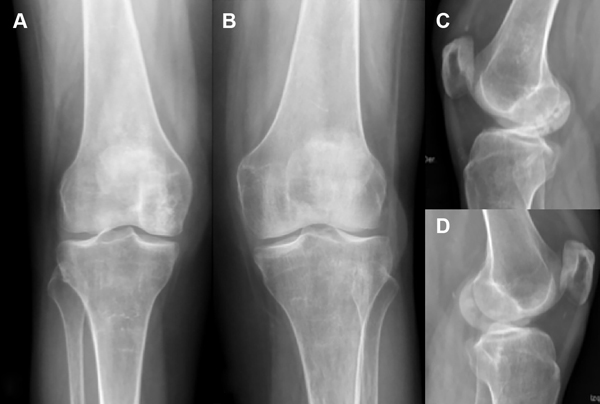

En la evaluación radiográfica se observaba un eje ligeramente valgo, de 6º en el miembro inferior izquierdo y un eje neutro con 8º en el derecho (fig. 1A), con incipientes signos de pinzamiento articular medial bilateral. Se veía una imagen radiolúcida, de contornos escleróticos proyectada en la superficie del cóndilo interno de la rodilla derecha, junto a una rarefacción ósea difusa del fémur distal y la tibia proximal bilateral (figs. 1B-C-D-E).

Figura 1: Radiografía de ambas rodillas. A) Escanograma frente, eje mecánico neutro. B) Rodilla derecha frente. C) Rodilla izquierda frente. D) Rodilla derecha perfil con imagen radiolúcida en la superficie del cóndilo interno, junto a rarefacción ósea difusa. E) Rodilla izquierda perfil con rarefacción ósea difusa.

En las radiografías a los dieciocho meses (fig. 8), se observa menor rarefacción ósea en ambas rodillas a nivel de los focos de necrosis y mayor congruencia articular en la lesión osteocondral del cóndilo interno de la rodilla derecha. Sin cambios degenerativos precoces.

Figura 8: Control radiográfico de ambas rodillas a los dieciocho meses postoperatorios. A) Rodilla derecha. Rx frente. B) Rodilla izquierda. Rx frente. C) Rodilla derecha. Rx perfil. D) Rodilla izquierda. Rx perfil.